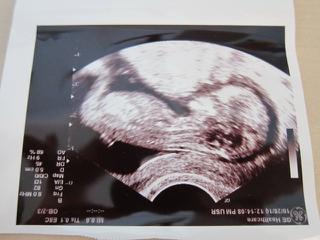

vcera sme boli na sone, videli sme s muzom nasho drobceka, ma 5 cm, cely cas sa hybal, plaval, mrvil sa, no aktivny cela mama, 😀 doktor nam vsetko poukazoval, aj sme videli prsteky na rukach, este nimi babo aj hybalo, aj srdiecko sme videli ako bilo, vsetky merania dopadli dobre, tak sa obaja tesime.

podla sona som na zaciatku 12 tt a podla MS v 14 tt.

A hodim sem aj fotecku, babo bolo otocene, tak davam dve fotky, my s muzom tam vidime aj ucho, oko a usta. 😀

inak zhodli sme sa s mm ze to vyzera na chlapca, podla tej foto z profilu, ale mohli by sme sa mylit, 😉